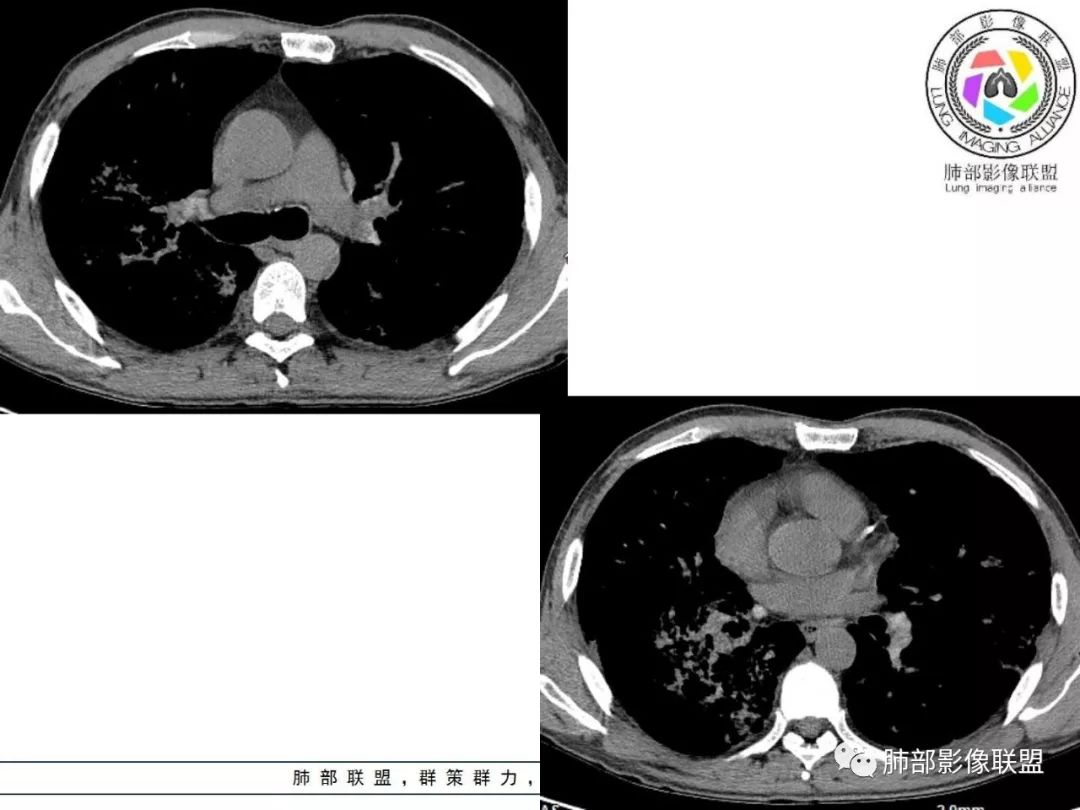

双肺间质性病变,中央间质增厚,胸膜下间质增厚,左侧胸膜肥厚,胸廓变小,肋间隙变窄。

胸部CT:两肺弥漫病灶,磨玻璃影,少许实变,部分累及胸膜,磨玻璃区可见囊?少许胸腔积液,两肺可见结节,支气管血管束增粗,小叶间隔增厚,支气管走形有扭曲扩张,可见纤维化。气肿、大泡。考虑:感染性病变,PCP?查下HIV,CD4,G等。鉴别结核、结缔组织病肺浸润。

55多男性,发热为主诉,体温38℃-39℃多,午后及夜间发热为主,峰值40℃,伴黄痰,CRP高,血糖正常,胸部CT:两肺弥漫病灶,磨玻璃影,少许实变,部分累及胸膜,两肺可见结节,似可见树芽,支气管血管束增粗,小叶间隔增厚,见肺气肿、大泡。考虑感染性病娈,肺结核可能性大。

患者中年男性,发热1月,体温38℃-39℃,峰值40℃,无畏寒、寒战,伴黄痰,CRP升高明显,降钙素原稍升高,血沉、血糖正常。胸部CT:两肺弥漫病变,磨玻璃影+点片渗出,部分累及胸膜,磨玻璃区边界清楚,少许胸腔积液,两肺支气管血管束增粗,小叶间隔增厚,部分支气管走形有扭曲扩张,可见肺气肿、右肺尖肺大泡及部分纤维化改变。综合考虑:感染性病变。结核或PCP可能性大,鉴别风湿免疫、结缔组织疾病肺浸润和腺癌等恶性病变。

胸部CT:两肺弥漫病灶,中央间质分布为主,部分位于胸膜及叶间裂旁,磨玻璃影,斑片影,部分实性结节,肺气囊,支气管血管束增粗,小叶间隔增厚,叶间裂不均匀增厚,支气管走形有扭曲扩张,可见纤维化、气肿、大泡。考虑:LIP加MALT。鉴别PLCH、PCP、结核、结缔组织病肺浸润。

双肺弥漫性病变,多发磨玻璃密度及小叶间隔增厚,大部分沿支气管血管束分布,伴支气管轻度扩张,以午后及晚上发热为主,考虑感染性病变,间质性结核可能大,另双肺多发肺气囊,LIP待排

病变一般沿血管支气管束分布或小叶分布,一般上肺多于下肺(这与常见继发性肺结核分布相若)。

2. 肺气肿背景(小叶中心性肺气肿);双肺多发病灶整体沿血管支气管束及胸膜下分布,以上叶及下叶背段分布为主,有实变及GGO,边界清楚,有树芽,小叶间隔及中央间质增厚,叶间裂见到多发结节,部分支气管不规则牵拉扩张,提示病灶纤维化明显,结合临床病史,考虑病灶为间质性感染,肺门及纵隔内有钙化淋巴结,小叶间隔结节,考虑淋巴道增值性疾病可能,综合常规要怀疑间质性肺结核。